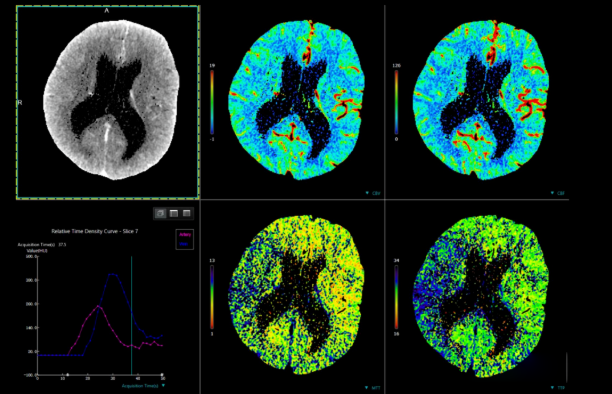

4、CT灌注成像:

最新CT灌注成像对临床鉴定肝、胰和骨骼的良恶性肿瘤以及急慢性脑缺血的诊断具有巨大价值。